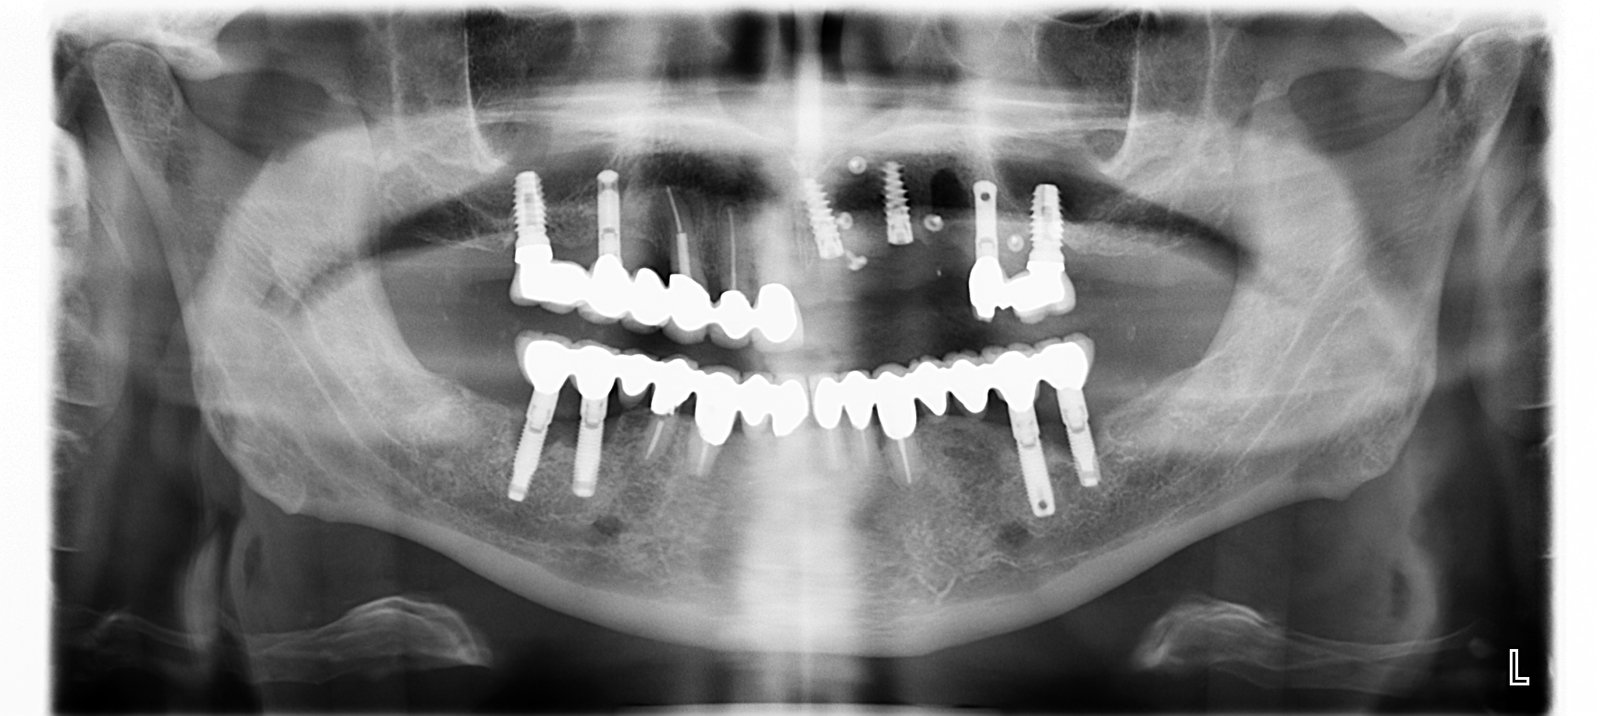

Queridos compañeros, me llega este caso de una persona muy especial y amiga de Barcelona. No manejo más información pero la panorámica es excelente. Gracias